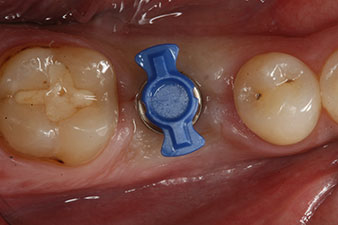

Fig. 1: Initial clinical situation after healing of extraction alveolus 36: The bone base is wide and there is sufficient keratinized gingiva.

Fig. 4: SmartPeg measuring posts screwed on to measure the implant stability quotients with the integrated W&H Osstell ISQ module.

SmartPeg